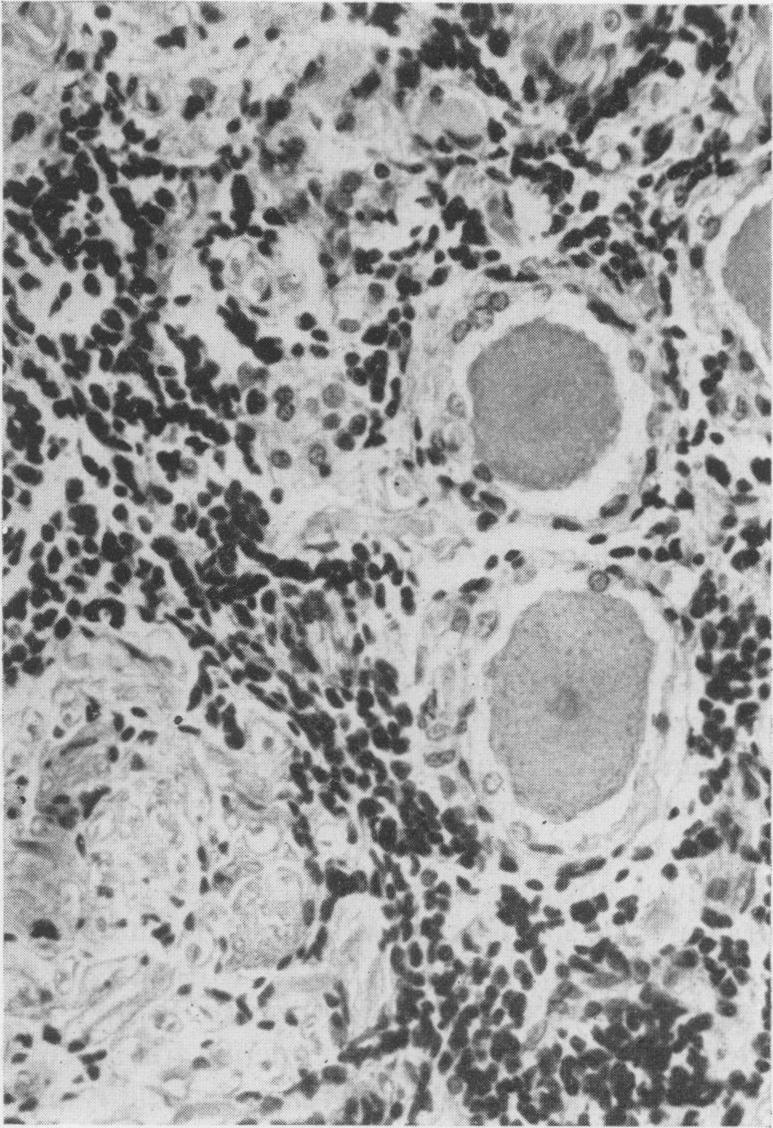

The clinical and pathological features of 63 cases of post-mortem-proved diffuse infiltration of the leptomeninges by tumour are presented. A wide variety of tumours of the nervous system, both primary and secondary, was found to give rise to such involvement, with adenocarcinoma having a particular propensity to behave in this manner. Dysfunction of cranial and spinal nerves, a confusional state and headache were prominent clinical features. Examination of the cerebro-spinal fluid was found to be less useful diagnostically in cases of primary tumours of the nervous system with leptomeningeal involvement than in cases of diffuse infiltration of the meninges by carcinoma.